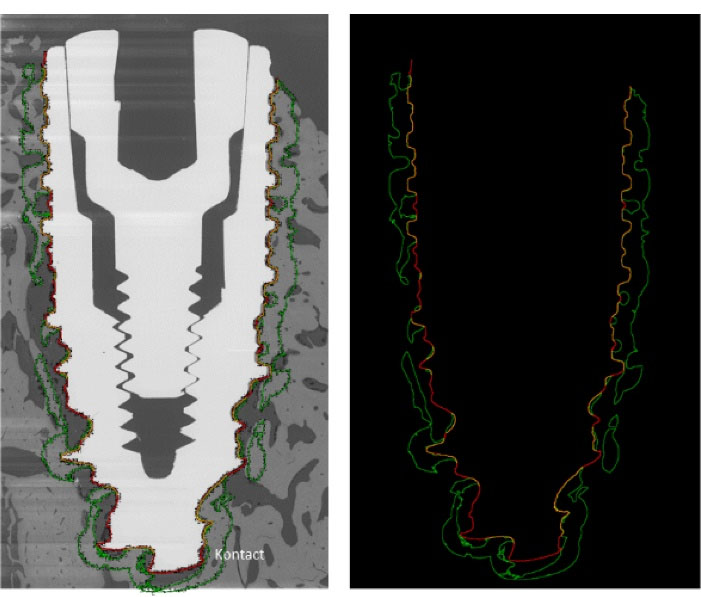

Each remaining second half-block was used to perform back-scattered electron microscopy (BSEM; Tabletop TM3000, Hitachi) to quantify bone-implant contact (BIC index) and bone surface to total surface ratio (BS/TS) at a distance of 0.5 mm around the implant. Contiguous images of the implant and the surrounding bone tissue were obtained with a magnification of × 50 and a motorized, programmable stage (Debel). On these BSEM images, the titanium implants appeared in white/light grey, the mineralized bone in grey and the non-mineralized tissue in black (Figure 5). BIC and BS/TS histomorphometric measurements were performed using ImageJ software (Figure 5).

Figure 5.

Example of BSEM image and its analyze with ImageJ software. The red line shows the dental implant edges, the yellow line shows the bone/implant contact, the green line delineates the bone at a 0.5 mm distance around the implant.